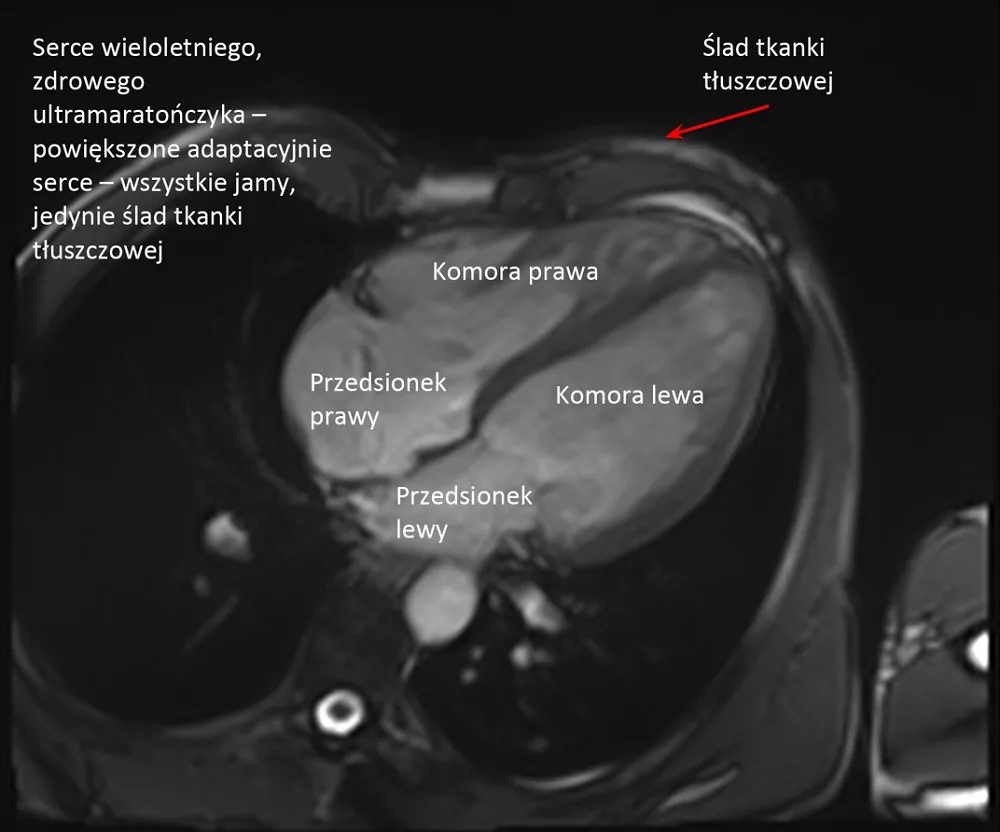

– Organizm osoby biegającej długo i duże objętości, trenującej wiele godzin tygodniowo, podlega tak zwanym zmianom adaptacyjnym. Jestem kardiologiem, więc powiem jak to wygląda patrząc od strony serca: zwalnia się rytm, serce jest bardziej spokojne, powiększają się jamy serca.

Tak, bo serce takiego biegacza bije 40 razy na minutę i jest powiększone. I taki lekarz mówi, że to bardzo niedobrze i żeby jak najszybciej zaprzestać biegania, a przynajmniej mocno zmniejszyć jego intensywność. Tymczasem... w większości wypadków są to właśnie normalne zmiany adaptacyjne, a organizm w ten sposób przystosowuje się do dużej intensywności, szczególnie jeśli trwa to latami.

Obu komór i obu przedsionków. One wszystkie powiększają się symetrycznie. Grubieje także trochę mięsień, natomiast raczej nie poszerza się aorta. Kurczliwość mięśnia sercowego w spoczynku może być na granicy dolnej normy, bo ono wtedy odpoczywa, natomiast w wysiłku radzi sobie i reaguje znakomicie.

W porównaniu do grupy kontrolnej, czyli mężczyzn w tym samym wieku nie uprawiających sportu, nie stwierdziliśmy żadnych cech uszkodzenia mięśnia sercowego czy anomalii w funkcjonowaniu układu krążenia, za to większość parametrów była znacznie korzystniejsza: cholesterol był niższy, tkanka tłuszczowa mniejsza, lepsze ciśnienie krwi. To wszystko pokazuje, że ultra jest korzystne dla zdrowia serca.